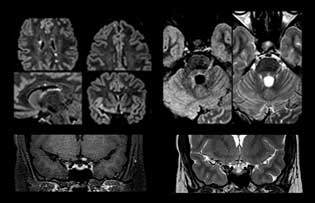

Wenn ein Verdacht auf multiple Sklerose (MS) besteht, muss das Klinikteam schnell zu einer Diagnose kommen, damit die Behandlung so bald wie möglich beginnen kann. „Eine Schwierigkeit bei der Bildgebung ist, dass MS-Läsionen im Gehirn und in der Wirbelsäule sehr klein sein können“, erläutert Dr. Savatovsky. „Wir benötigen eine präzise Bildgebung, um exakt zu bestimmen, wo sich die Läsion befindet, das heißt, wir brauchen hochwertige Bilder in sehr hoher Auflösung, vorzugsweise in 3D[1]. Wir müssen uns sicher sein, ob eine hohe T2-Signalintensität auf MS hinweist oder lediglich aspezifisch ist. Außerdem wünschen wir uns eine sehr gute Visualisierung von aktiven Läsionen.“

„Ingenia 3.0T liefert uns eine sehr gute Bildqualität mit hohem Signal-Rausch-Verhältnis, auch wenn wir die Auflösung ausreizen. Bei FLAIR-Bildern haben wir zum Beispiel eine isotrope Auflösung von 0,9 mm. Ingenia ermöglicht uns die Nutzung von 3D-T1-TSE mit BrainView, was eine bessere Empfindlichkeit als die 2D-Spinecho-Bildgebung[2] und die 3D-Gradientenecho-Bildgebung aufweist. Ingenia liefert auch hoch reproduzierbare Untersuchungen, was bei der MS-Bildgebung wichtig ist, damit Folgeuntersuchungen zu verschiedenen Zeitpunkten auf dieselbe Weise durchgeführt werden.“

Für die MS-Bildgebung im Gehirn nutzt Dr. Savatovsky 3D-FLAIR als Basissequenz, um die Läsionen darzustellen sowie die jeweilige Situation und die Läsionsbelastung zu beurteilen. „Wir zählen die Läsionen an jeder Stelle, um zu bestimmen, ob die Kriterien der Erkrankung erfüllt sind. Dafür wird eine T2-gewichtete Sequenz verwendet, weil unsere Neurologen diese gewohnt sind. Wir vergleichen die Läsionsbelastung unter FLAIR mit einer 3D-T1-Postkontrastsequenz, damit wir feststellen können, ob die Läsionen alt oder neu sind. In der Regel verabreichen wir das Kontrastmittel vor der Aufnahme des Patienten in das System, weil sich dadurch die Untersuchungsdauer verkürzt und die Visualisierung aktiver Läsionen möglich wird, die im Allgemeinen nach mehreren Minuten deutlicher dargestellt werden. Wenn sich eine differenzielle Diagnose als schwierig herausstellt, nutzen wir weitere Sequenzen wie die Suszeptibilitätsbildgebung, da einige fokale MS-Läsionen in der Mitte eine kleine Ader aufweisen[3].“

„Für eine MS-Bildgebung in der Wirbelsäule beinhaltet die Basisuntersuchung eine sagittale T2-gewichtete und eine sagittale T1-gewichtete Postkontrastsequenz in der gesamten Wirbelsäule. Diese erfolgen in zwei Stapeln und mittels dünner Schichten, zum Beispiel 2 mm ohne Lücke. Wie im Gehirn wird mit der T2-gewichteten Postkontrastsequenz die gesamte Läsionsbelastung visualisiert und sie hilft bei der Beurteilung, ob eine Läsion alt oder neu ist. Gelegentlich fügen wir eine T1-Inversion Recovery hinzu, die eine sehr hohe Empfindlichkeit besitzt, wenn wir mit T2 keine Läsionen finden“, so Dr. Savatovsky weiter. „Wenn wir zusätzlich eine Kontrastverstärkung außerhalb der Wirbelsäule feststellen, handelt es sich üblicherweise nicht um MS, sondern um eine andere Entzündungsart.“